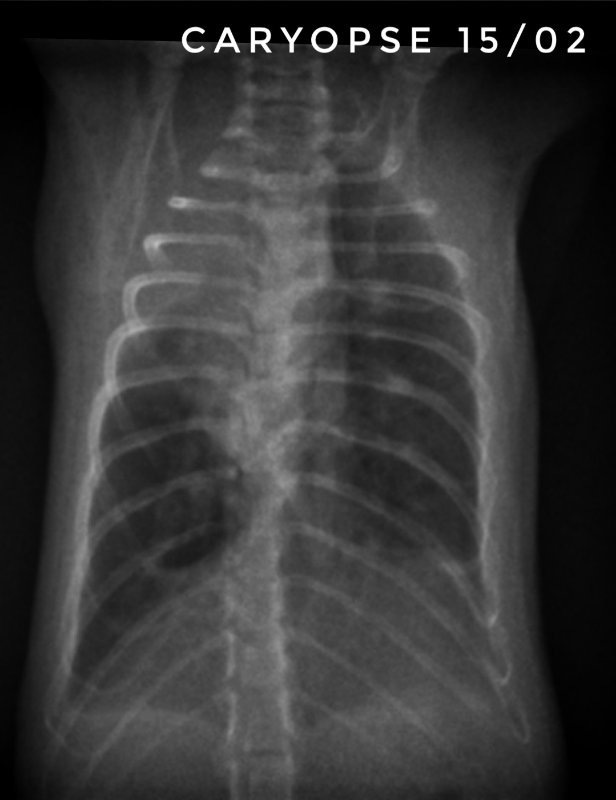

Toujours pour ceux que ça intéresse, les dernières  radios et le suivi du poids (Pyridion a commencé à perdre du poids le 04 mars, traitement changé le 08)

Il nous reste donc 3 malades : Drupe, Caryopse et Pyridion.

Drupe va vraiment mieux, poumons encore touchés mais mieux quand même (mais décidément c'est bien long).

Pyridion a eu un vrai mieux la semaine dernière et grosse dégradation là. Les radios n'ont pas bougé depuis 3 semaines...

Et Caryopse, mon petit nain (180g) va physiquement pas trop mal, c'est à dire qu'il respire vite mais pas pire quoi... par contre ses radios sont... bref, le veto ne s'y attendait pas du tout lui non plus... en gros, petit mieux là où il était touché avant mais dégradation asur le reste du poumon...